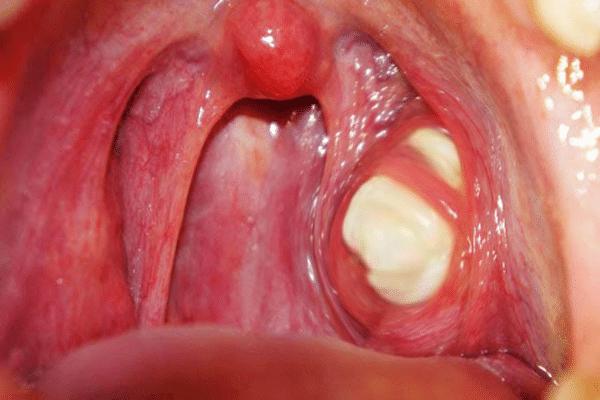

Οι πέτρες των αμυγδαλών ή οι αμυγδαλόλιθοι είναι μικροί, ασβεστοποιημένοι σχηματισμοί που αναπτύσσονται στις σχισμές των αμυγδαλών. Αυτές οι πέτρες αποτελούνται από υπολείμματα όπως νεκρά κύτταρα, βλέννα, σωματίδια τροφής και βακτήρια, τα οποία συσσωρεύονται και σκληραίνουν με την πάροδο του χρόνου. Οι πέτρες αμυγδαλών μπορεί να ποικίλλουν σε μέγεθος, από μικροσκοπικούς κόκκους έως μεγαλύτερους, πιο εμφανείς σχηματισμούς και συχνά έχουν λευκό ή κιτρινωπό χρώμα.

- Πρησμένες αμυγδαλές